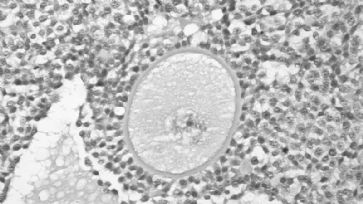

Der Frauenkörper als Verhandlungsort von Politik oder über die Illusion, als Frau frei zu sein. /

Jede Herrschaftsform etabliert sich über den Frauenkörper. Wer, wann, wie, warum, ob oder nicht Kinder gebären darf oder gar Sexualität leben, ist Politik, nicht Natur. Punkt. Fertig. Schluss. Amen. Da nützen alle Relativierungsversuche in der «Genderfrage» nichts, denn im Kern geht es um die Verfügung des weiblichen Körpers. Es geht auch nicht um Rollenzuweisung oder sonstiges Blabla, es geht im Wesentlichen um die Gebärmutter und um die Klitoris und deren gesellschaftliche, politische, technische, kulturelle, wirtschaftliche und wissenschaftliche Verfügung. So erklärt sich Egg-Freezing, wissenschaftlich propagierte Sklavenherrschaft via Leihmütter und medial inszenierte «Kauf mich und Fick-Mich» -Kultur, die den Job, anderen Menschen, ihre Löcher zur Verfügung zu stellen und ihren Körper inklusive Organe als «Tätigkeit wie jede andere» verschleiert (siehe Link). So erklären sich alle Religionen inklusive Klassenkämpfe. Wenn ganze Gesellschaften mit entsprechender Erzählung, Frauenkörper verschleiern, entblössen, zerstückeln, verkaufen, zur Verfügung stellen, von klein auf zum Dienst am Mann trainieren etc., dann hat dies nichts mit Kultur, sondern nur mit Politik zu tun. Wenn sich Frauen «freiwillig» der allmächtigen Anpassung der jeweiligen Mehrheitsgesellschaft unterwerfen, hat dies nichts mit «Freiheit» zu tun, sondern mit Politik und Herrschaft. Wie wäre es, mal solche Geschichten zu erzählen statt ständig so zu tun als wäre alles eine Frage der Sozialisation, der Religion, der Wirtschaft oder Herkunft? Oder in den Worten von Ta-Nehisi Coates: «In America, it is traditional to destroy the black body, it is heritage.» Darauf würde ich sagen: «In the world it is traditional to use, destroy and sell women´s bodies, it is called culture. When it comes to women´s bodies, human science and life science want to bringt us to the edge of oblivion.» Jedes politische System speist seine Legitimation, Funktion und Stabilität aus einem entsprechenden Menschenbild. Jedes politische System kann an der Herrschaftstechnik am weiblichen Körper erzählt werden. Es wäre schön, der Diskurs könnte einfach mal diese Erkenntnis voraussetzen statt über «Männer» und «Frauen» zu reden und immer was ganz beliebiges, hippes, zerstückeltes oder propagandamässiges zu erzählen. Der weibliche Körper ist Ausgangspunkt und Etablierung von Herrschaft. Insofern war «Köln» nichts Neues. «Köln» war einfach sichtbarer als andere Herrschaftstechniken (und zwar auf allen Seiten: Polizei, Behörden, Täter und Medien). Und ja: Selbstverständlich sind die Kämpfe der Gegenwart direkt auf den weiblichen Körper gerichtet. Denn hier entscheidet sich, einmal mehr, die Zukunft der Menschheit. Wäre dies einmal klar, könnten wir die Geschichte ganz anders schreiben und damit auch die Zukunft.